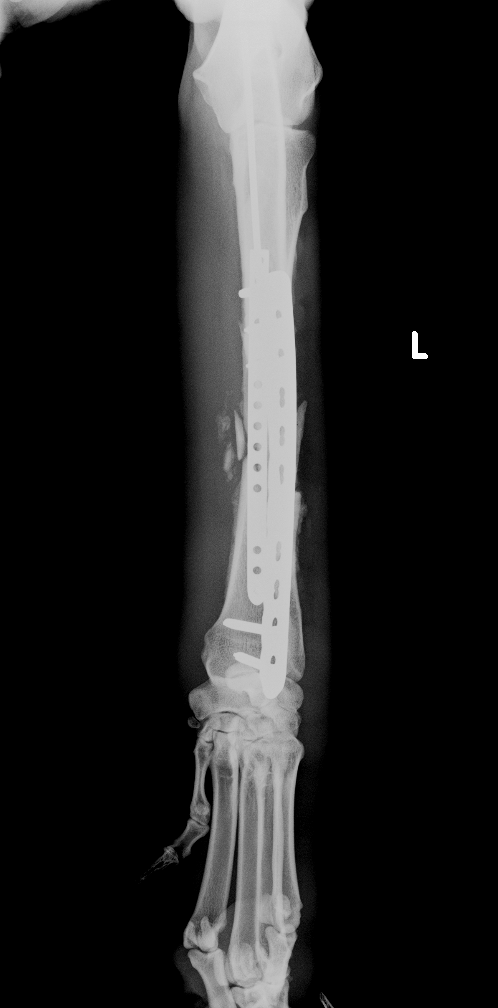

左前肢挙上し、軟部組織の腫脹が認められました。レントゲン、CT検査より橈骨・尺骨の粉砕骨折が認められました

診断と治療

左橈骨・尺骨の粉砕、解放骨折と診断し、橈骨にはLCPのダブルプレート、尺骨には髄内ピンによる治療を行いました

after